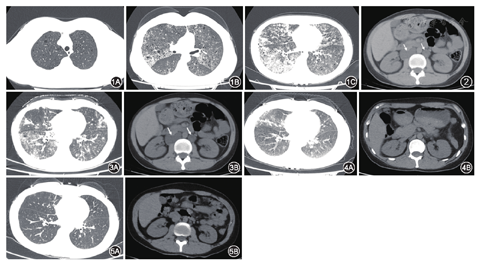

患者女性,32岁。因咳嗽咳痰1年,气喘半年,加重1周于2017年4月12日入院。2016年4月起患者无明显诱因出现咳嗽咳痰,未予特殊治疗。2016年12月患者因气喘住院,胸部CT提示双肺散在小圆形透亮影,双肺散在斑片影,磨玻璃影。诊断间质性肺炎,予莫西沙星(0.4 g/d)及甲泼尼龙(40 mg/d)治疗7 d后出院,患者咳痰、气喘无明显改善。2017年4月初患者气喘加重,2017年4月5日门诊胸部CT提示双肺小囊状透亮影,小叶间隔增厚,双肺散在多发斑片影,磨玻璃影,右肺为重(图1),遂收住我科。体检:体温36.6℃,脉搏100次/min,呼吸20次/min,血压112/86 mmHg(1 mmHg=0.133 kPa)。双下肺听诊可闻及细湿啰音,心、腹体检未见明显异常。动脉血气分析:pH值7.40,动脉血氧分压(PaO2)56 mmHg,动脉血二氧化碳分压(PaCO2)32.6 mmHg,动脉血二氧化碳总量(TCO2)21 mmol/L,HCO3- 20.2 mmol/L,碱剩余−5 mmol/L,动脉血氧饱和度(SaO2)89%。实验室检查,白细胞计数6.14×109/L,红细胞计数4.79×1012/L,血红蛋白144.0 g/L,血小板计数289×109/L;丙氨酸转氨酶18 U/L,天冬氨酸转氨酶15 U/L,肌酐58 μmol/L,尿素氮4.30 μmol/L,甘油三酯0.96 mmol/L,钾3.61 mmol/L,钠140.9 mmol/L,血糖4.20 mmol/L;凝血酶原时间14 s,凝血酶原活动度89%,活化部分凝血活酶时间33.1 s,凝血酶时间18.7 s,纤维蛋白原3.13 g/L,国际标准化比值1.08;红细胞沉降率(1 mm/1h)、超敏C反应蛋白(<0.1 mg/L)、白细胞介素-6(2.82 ng/L)、降钙素原(<0.05 μg/L)均在正常范围。风湿免疫相关抗体(包括抗核抗体、抗双链DNA抗体、抗nRNP抗体、抗Sm抗体、抗SSA抗体、抗SSB抗体、抗Scl-70抗体、抗Jo-1抗体、抗着丝点B抗体、抗组蛋白抗体、抗核小体抗体、抗核糖体P蛋白抗体、抗Ro-52抗体)、类风湿因子(<20 IU/ml)、抗中性粒细胞胞质抗体胞质型和核周型、抗角蛋白抗体、抗心磷脂抗体均阴性。肿瘤标志物[甲胎蛋白4.03 μg/L,癌胚抗原1.33 μg/L,糖类抗原125 14.1 U/ml,糖类抗原15-3 18.8 U/ml,糖类抗原19-9 24.70 U/ml,糖类抗原72-4 0.58 U/ml,鳞状细胞癌相关抗原0.4 μg/L,总人绒毛膜促性腺激素(β-hCG)<0.10 mIU/ml]均正常。心电图、心脏彩色超声未见异常。患者气喘明显,肺部囊状病变多,行肺功能检查易诱发气胸,风险较大,故未行肺功能检查。因患者为年轻女性,前期抗生素和糖皮质激素治疗效果不佳,胸部CT提示多发小囊性影,考虑LAM,故测血清血管内皮生长因子D(VEGF-D)水平为11 370.2 ng/L。痰乳糜试验(苏丹红染色)阳性。腹部CT提示,腹膜后可见多发低密度团块影(图2)。考虑LAM合并乳糜肺炎,予西罗莫司(2 mg,1次/d)治疗20 d后,查血药浓度为14.32 μg/L,将西罗莫司改为单日口服1 mg,双日口服2 mg,患者气喘症状明显改善后出院。继续西罗莫司维持治疗,定期复诊调整西罗莫司剂量(1~2 mg,1次/d),使其血药浓度维持在5~10 μg/L。2个月后复诊时,西罗莫司改为单日口服1 mg,双日口服2 mg,查血药浓度为8.62 μg/L;复查胸部CT示,肺部病变改善(图3A);腹部CT示,腹部病灶缩小(图3B)。8个月后复诊时西罗莫司口服1 mg,1次/d,查血药浓度为4.94 μg/L;复查胸部CT示,肺部病变较前好转(图4A);腹部CT示,腹膜后未见到明显病灶(图4B)。18个月后复诊时西罗莫司口服1 mg,1次/d,查血药浓度为4.78 μg/L;复查胸部CT示,肺部病变明显好转(图5A);腹部CT示,腹膜后未见到明显病灶(图5B)。自2017年4月开始使用西罗莫司后,患者血清VEGF-D水平逐渐下降,6个月后为4 607.1 ng/L,9个月后为4 142.8 ng/L,18个月后为3 231.9 ng/L。